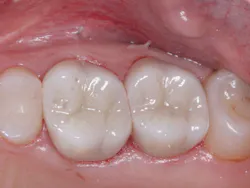

A: Full-zirconia restorations have been available for the past years or so. They have evolved from relatively unesthetic, opaque crowns and bridges to significantly improved restorations with acceptable esthetics (figures 1 and 2). Most dentists have noted that the majority of zirconia restorations are lighter in color than they requested on their lab order. The intense opacity of this material makes the restorations appear light in color. As the new generation of "esthetic zirconia" restorations continues to improve, this color problem will probably be overcome.

Figure 2: Full-zirconia restorations on the first and second molars show the significant improvement in color now available with full-zirconia restorations.